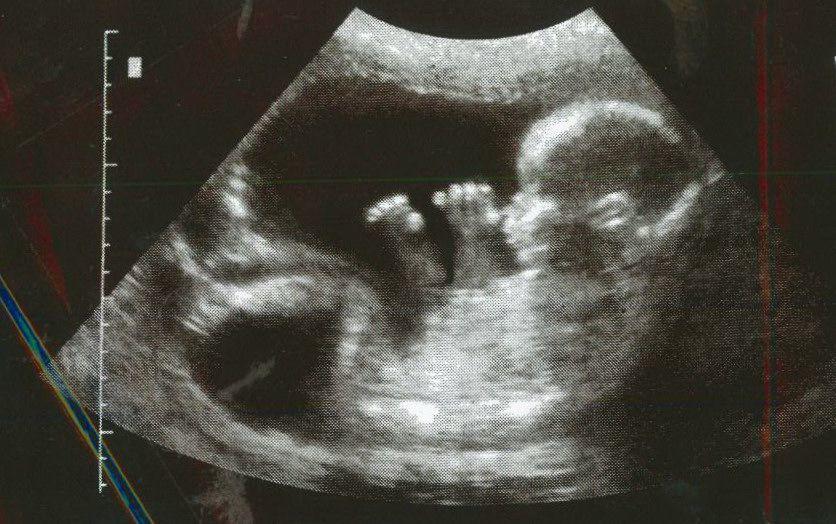

直到80年代,英国著名心理学教授Dr. Glenn Wilson(中译:葛籣. 威尔逊博士)就假说(hypothesize)2D:4D 比率的决定因素之一就是BB在妈妈的子宫内的性激素的暴露(sex hormone exposure in the womb)。

1998年,利物浦大学的心理学家Dr. John Manning(中译:约翰. 曼宁)发表了一篇论文,推断 2D:4D 比率是由BB在妈妈肚子里接触睾丸酮的量来决定的。

到了2011年, 科学家终于证明BB产前接触睾酮决定了2D:4D 比率。

2011年,发展生物学家Martin Cohn 和Zhengui Zheng对小鼠胎儿进行了实验, 他们在子宫内改变了睾丸激素的含量。他们发现的不仅仅是胎儿睾酮的数量决定了2D:4D 比率, 而是睾丸酮和雌激素(estrogen)之间的平衡。

睾丸激素浓度较高或雌激素水准低的小鼠有更多的男性像数比率(低2D:4D 比率), 而雌激素较高或睾酮较低的小鼠有较高的女性数位比率(高2D:4D 比率)。

Martin Cohn 和Zhengui Zheng认为, 这个在老鼠的发现,同样会发生在人类的身上。